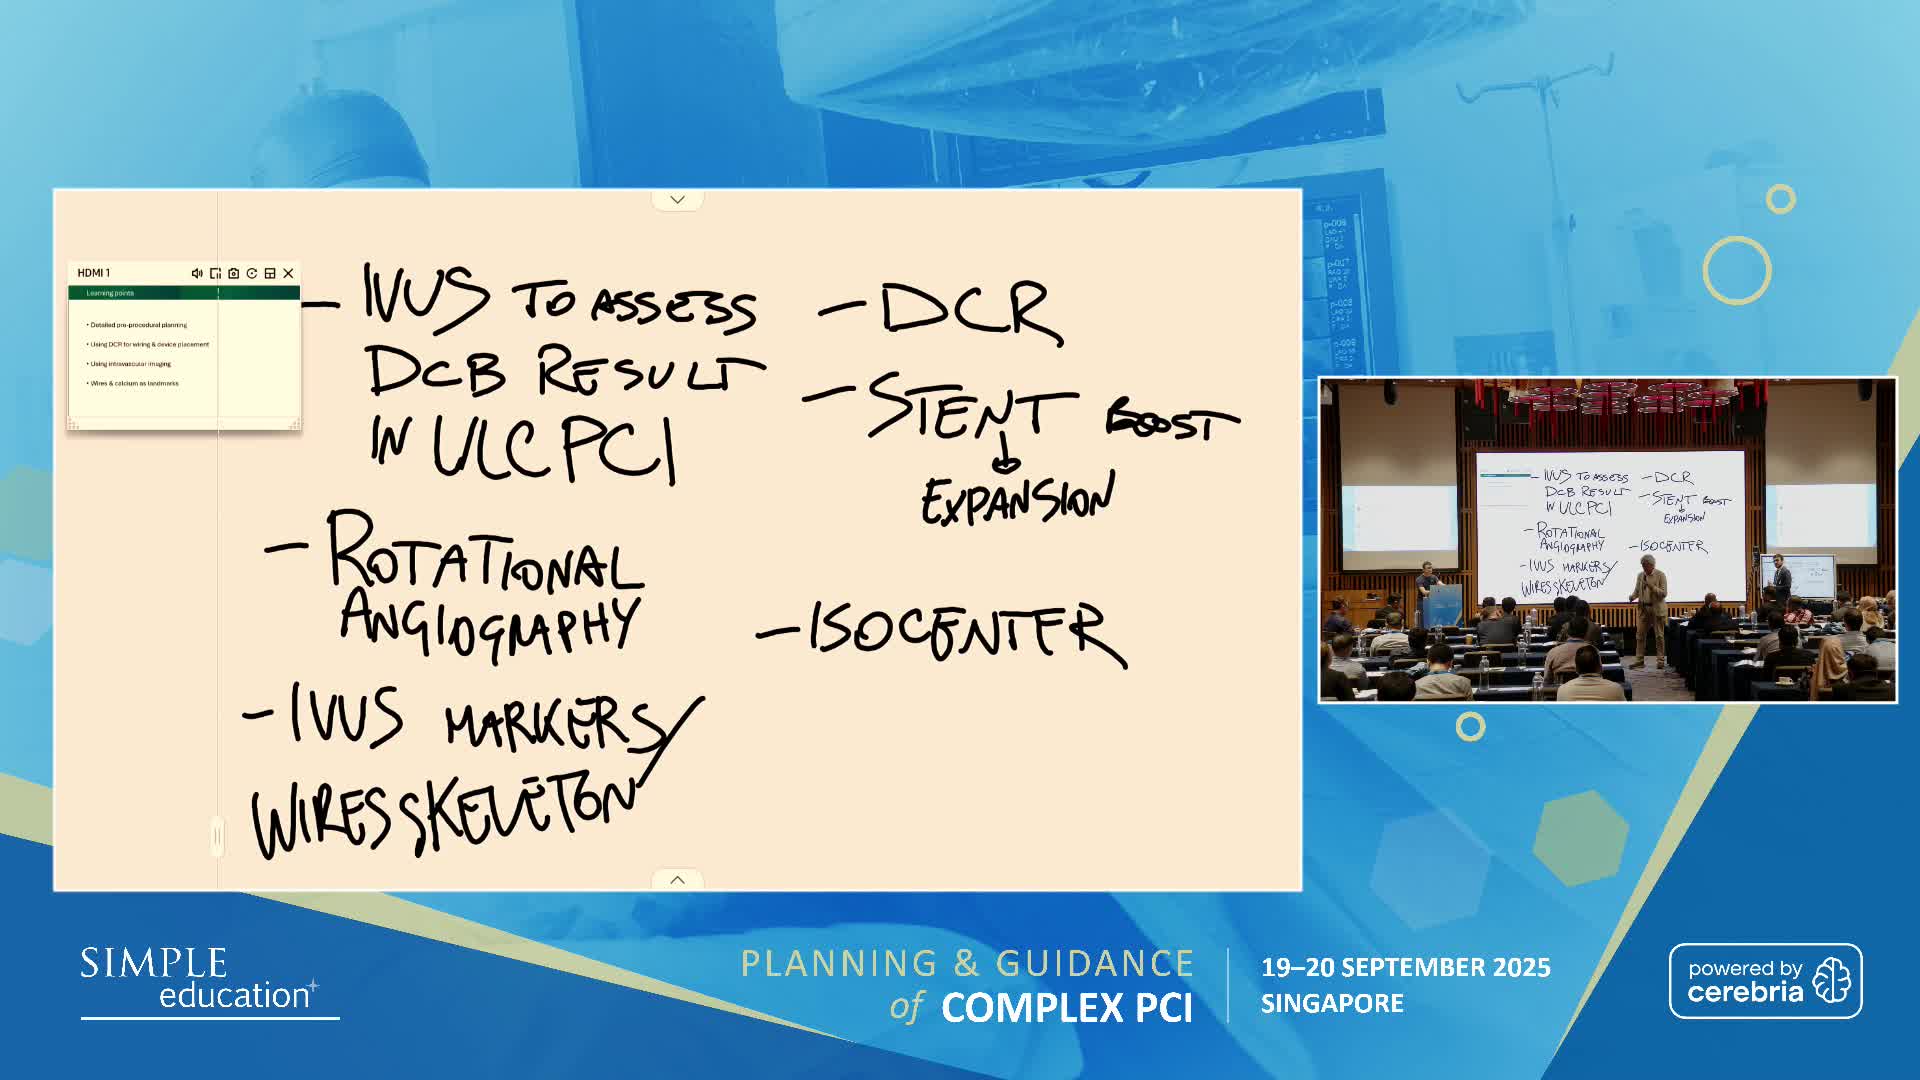

Ultralow Contrast PCI in complex and high risk patients - April 2024 Day One

Ultralow Contrast PCI in complex and high risk patients - April 2024 Day Two

Ultralow Contrast PCI in complex and high risk patients - November 2023 Day One

Ultralow Contrast PCI in complex and high risk patients - November 2023 Day Two

Ultralow Contrast PCI in complex and high risk patients - June 2023 Day One

Ultralow Contrast PCI in complex and high risk patients - June 2023 Day Two